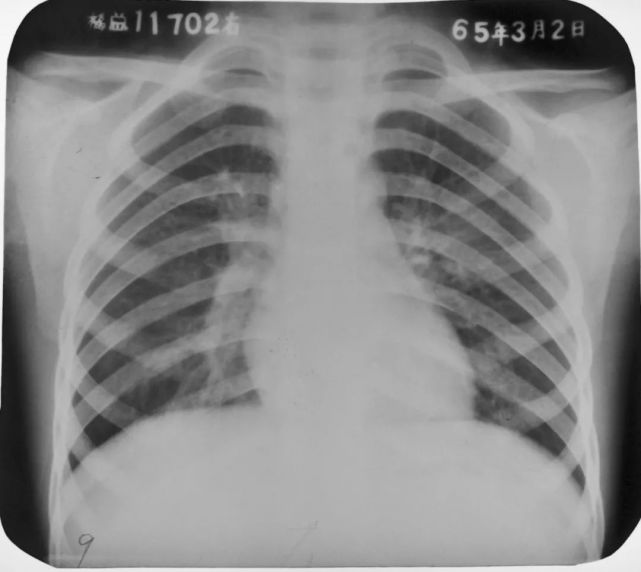

两下肺支气管肺炎

图片

胸部正位片示:两下肺可见不规则的小片状或斑片状边缘模糊的致密阴影,阴影密度不均